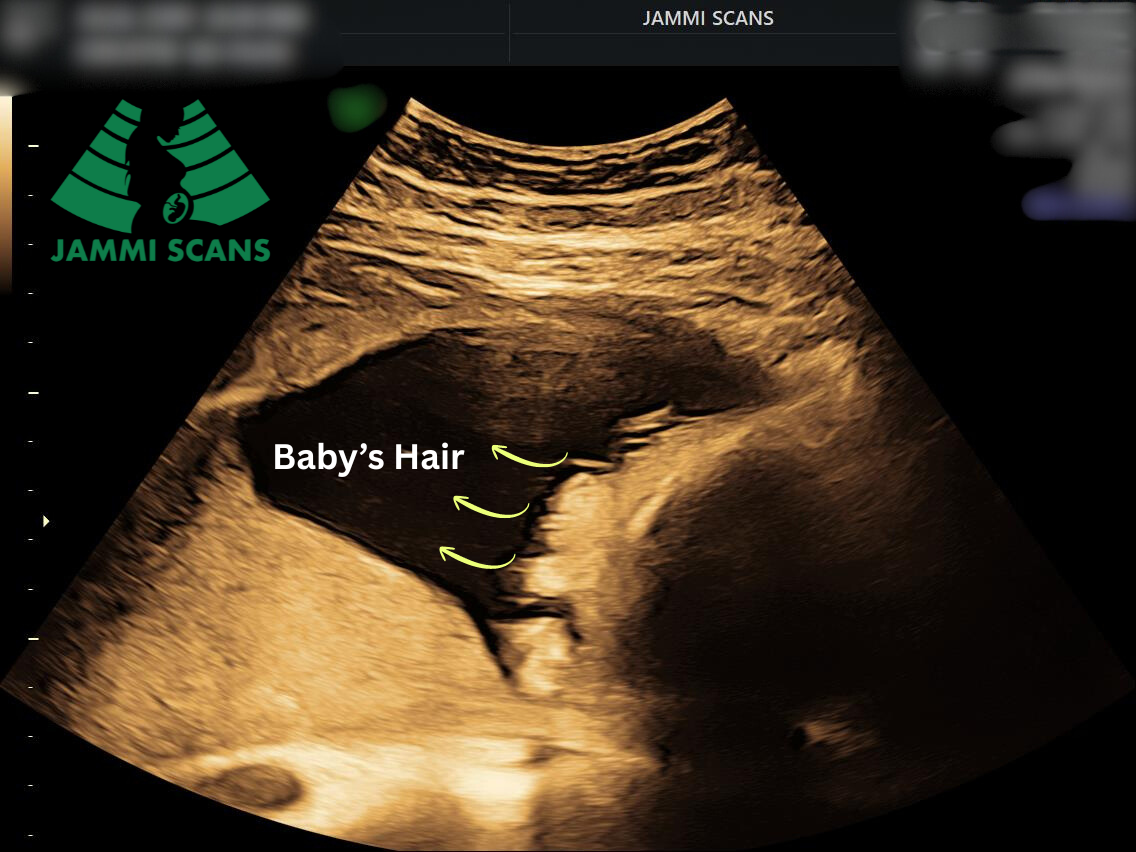

- A baby’s hair can sometimes be seen on an ultrasound, especially in the third trimester.

“At Jammi Scans, we’ve even spotted baby’s hair during a pregnancy ultrasound scan!”

Yes, in some cases, your baby’s hair can be seen during a pregnancy scan, especially in the later weeks of pregnancy.

However, it depends on various factors such as the stage of pregnancy, type of scan, and the baby’s position.

By 32–36 weeks, hair growth becomes more noticeable. During a Growth or Doppler scan, you may spot faint white lines or a fuzzy ring around the baby’s head.

In 2D scans, hair may appear as soft streaks, while 3D/4D scans can sometimes reveal individual strands if conditions are ideal.